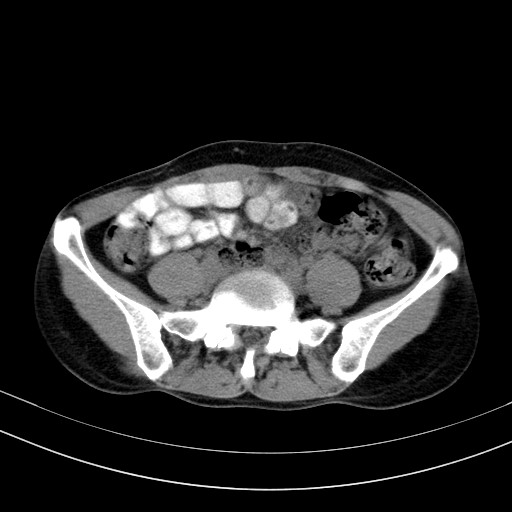

以下是引用随光逐影在2009-4-7 8:17:00的发言:[br]考虑宫颈占位性病变(宫颈癌?);建议行进一步检查。

以下是引用jiangjing在2009-4-7 16:46:00的发言:[br]宫颈增大,结构不清,右侧附件区可疑囊样占位,建议增强及mri 检查